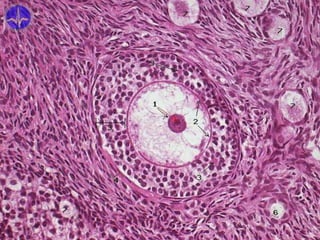

Primary follicle

1 – folliculus primarius

2 – folliculocyti

4 – zona pellucida

5 – folliculus

primordialis

8 – textus connectivus

interstitialis

9 – theca folliculi

• epithelium stratificatum cuboideum

• prominent basal lamina and zona pellucida

• theca folliculi (follicular sheath)

– thickening of adjacent connective tissue and

stromal cells

Folliculi ovarici secundarii

Secondary follicles